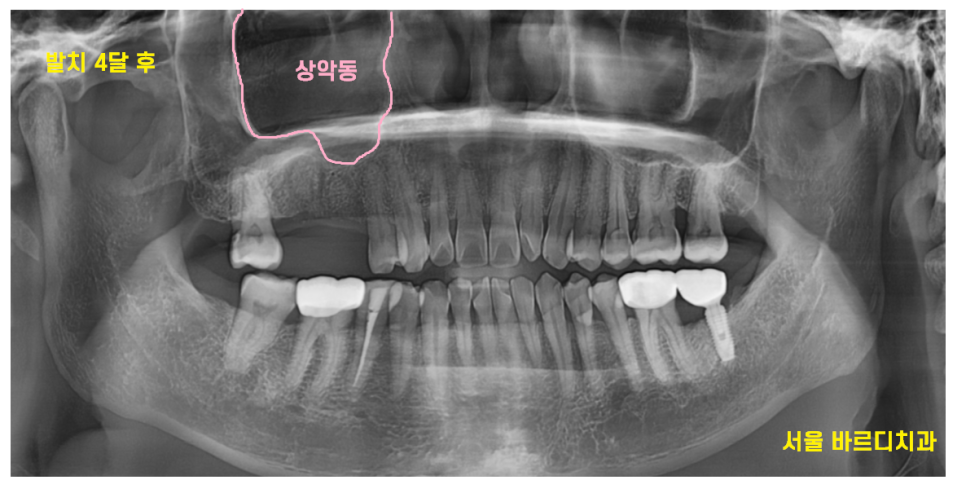

23.07.14

발치 후 4달

계속 뼈가 만들어 지는 과정을 지켜보았습니다.

치아 뾰루지가 한두번 났을 때

뽑고 임플란트를 했으면

이렇게까지 안기다리셔도 됐을텐데ㅠㅠ